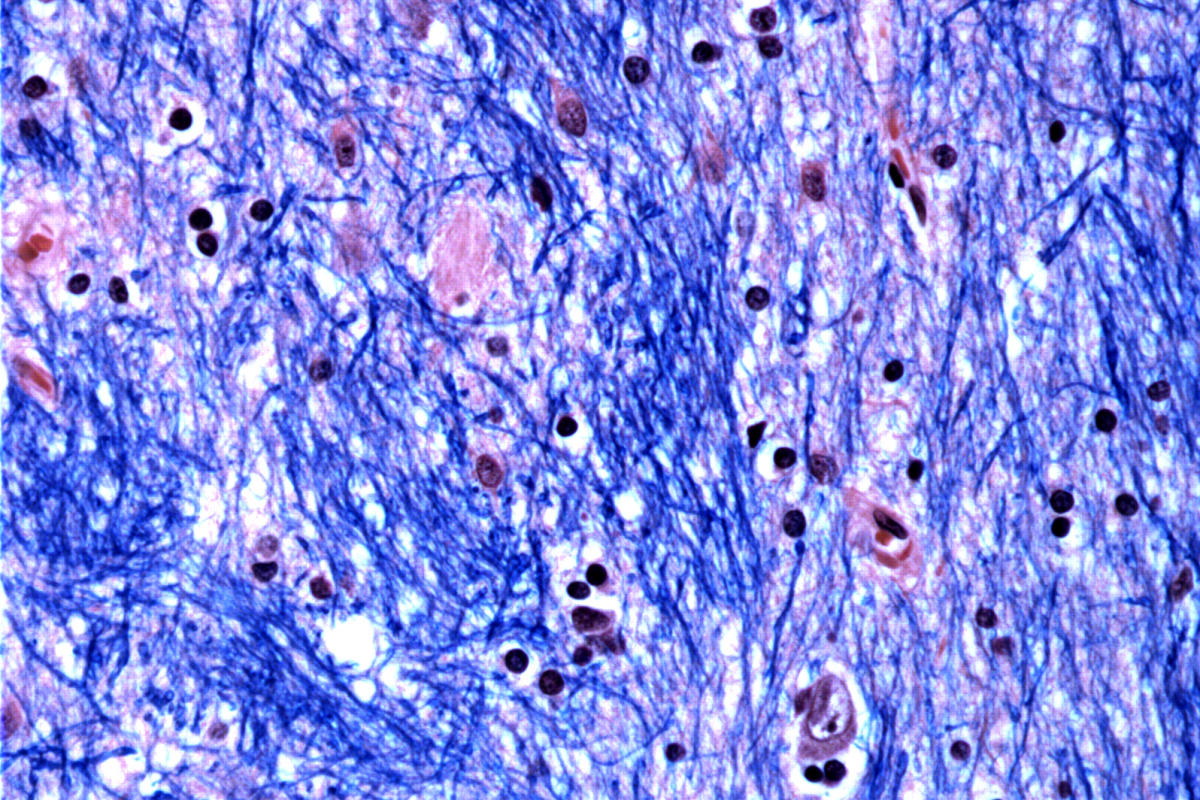

وقام علماء في معهد برود التابع لمعهد ماساتشوستس للتكنولوجيا وجامعة هارفارد ومستشفى ماكلين في ماساتشوستس وكلية الطب بجامعة هارفارد بدراسة أنسجة المخ التي تبرع بها 53 شخصا مصابين بمرض هنتنغتون و50 شخصا غير مصابين به، وقاموا بتحليل نصف مليون خلية.

وركزوا على طفرة هنتنغتون، التي تتضمن امتدادًا من الحمض النووي في جين معين حيث يتكرر تسلسل مكون من ثلاثة أحرف – CAG – 40 مرة على الأقل. أما بالنسبة للأشخاص الذين لا يعانون من المرض، فيتكرر هذا التسلسل من 15 إلى 35 مرة فقط. واكتشفوا أن مسارات الحمض النووي التي تحتوي على 40 أو أكثر من هذه “التكرارات” تتوسع بمرور الوقت حتى يبلغ طولها مئات من الـ CAGs. بمجرد وصول CAGs إلى عتبة حوالي 150، فإن أنواعًا معينة من الخلايا العصبية تمرض وتموت.